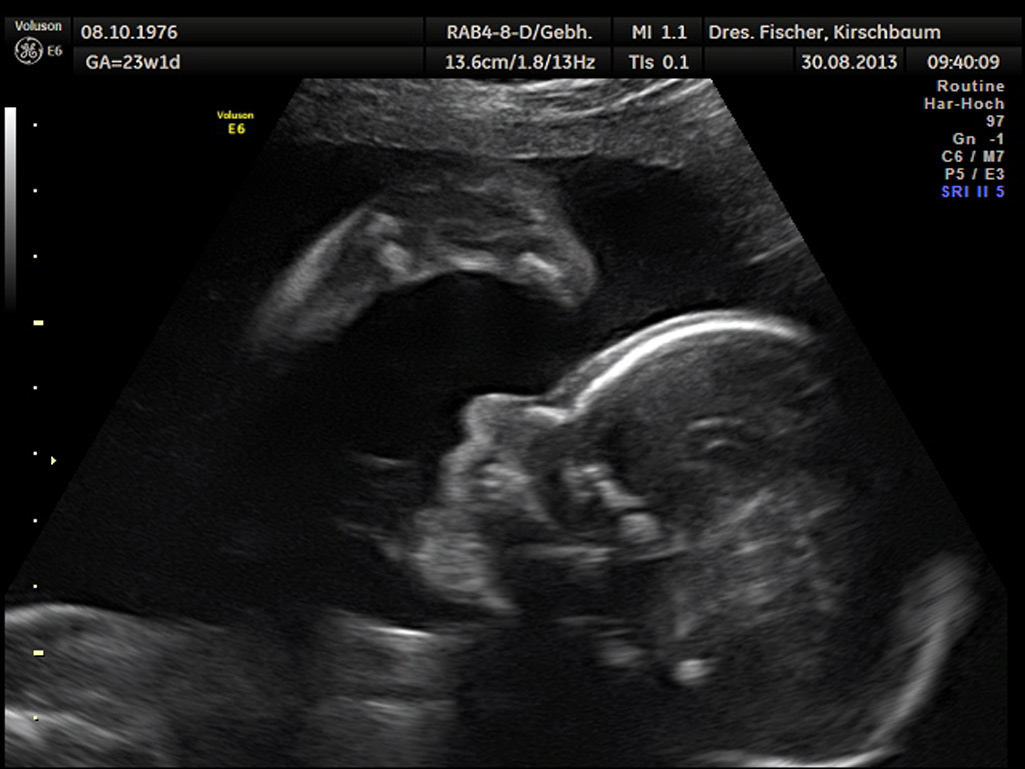

Eine Schwangerschaft gehört zu den schönsten Ereignissen im Leben einer Frau. In dieser spannenden Phase ihres Lebens wollen wir sie betreuen, begleiten und Ihnen gemeinsam mit unserer Hebamme mit Rat und Tat zur Seite stehen.

Die Schwangerschaft dauert 40 Wochen (Schwangerschaftswochen, oft als Kurzform SSW), gerechnet nach dem ersten Tag der letzten Regelblutung. In dieser Zeit führen wir regelmäßige Untersuchungen durch.